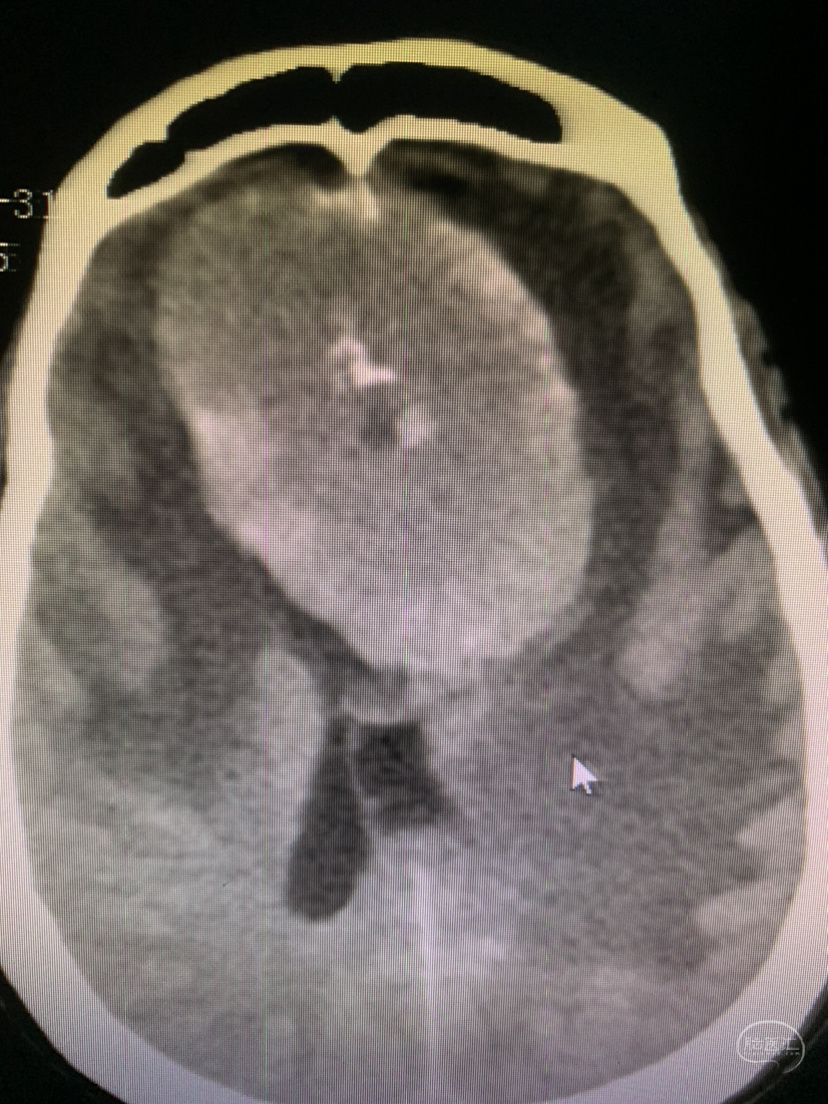

术前术后对比

术后CT